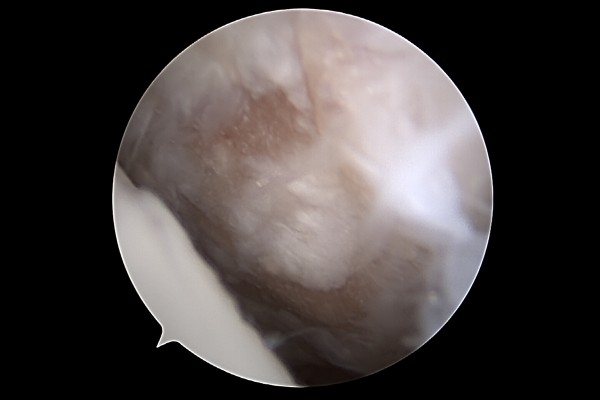

교정술 시행 전 관절내시경을 이용하여 발목 상태를 확인했을 때, 먼저 정상적으로 연골이 덮여있는 부분이 확인됩니다.

반면 안쪽(내측) 복숭아뼈 맞닿는 부분을 보면 관절이 맞닿아 까진 것이 확인됩니다.

거골의 안쪽도 연골이 파여진 것을 확인할 수 있습니다.